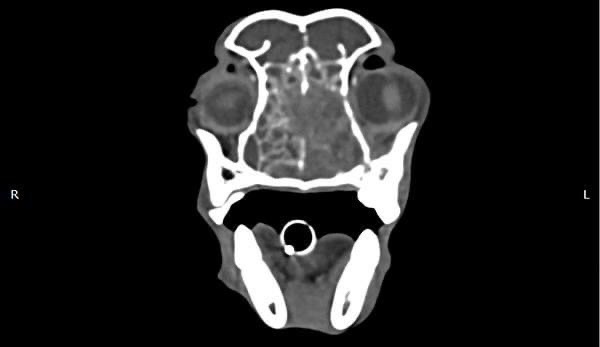

狗狗 肺臟腫瘤 Pulmonary carcinoma

持續數月的咳喘 他院懷疑心臟問題轉診來築心,經由電腦斷層掃描及胸腔採樣

確診為惡性腫瘤,由於腫瘤已經擴散不適合外科手術,主人最後決定使用化療延長壽命